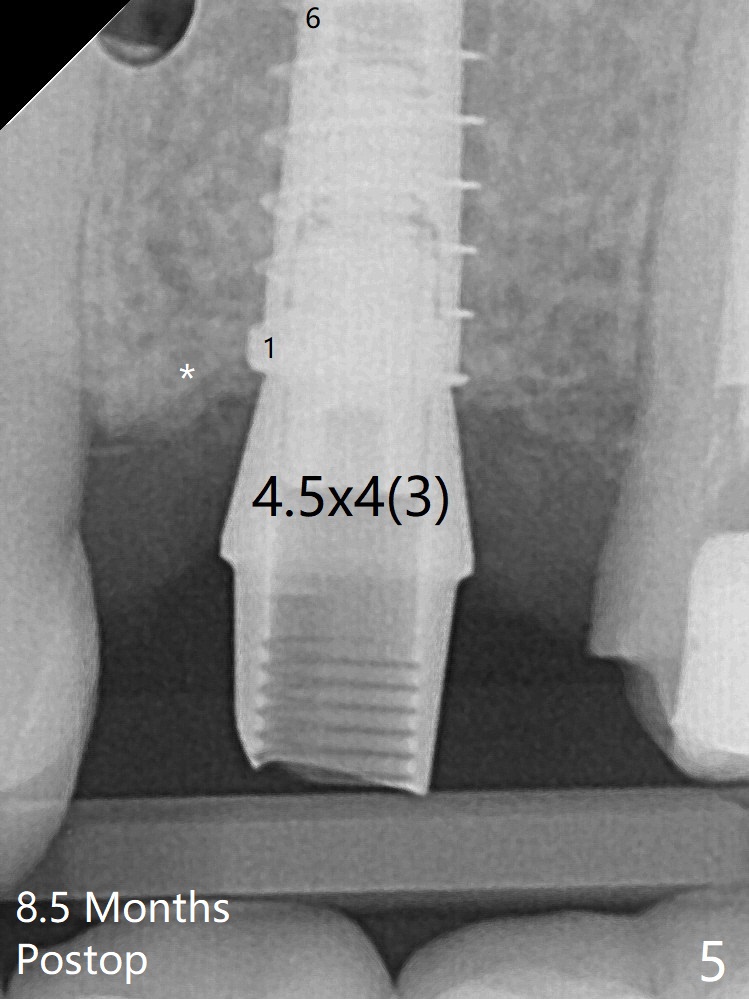

There is a gap mesial to the implant between the 1st and 7th threads immediate postop (Fig.3).  The gap is absent between 1st and 6th threads 8.5 months postop (Fig.5) with formation of the dense crestal bone.